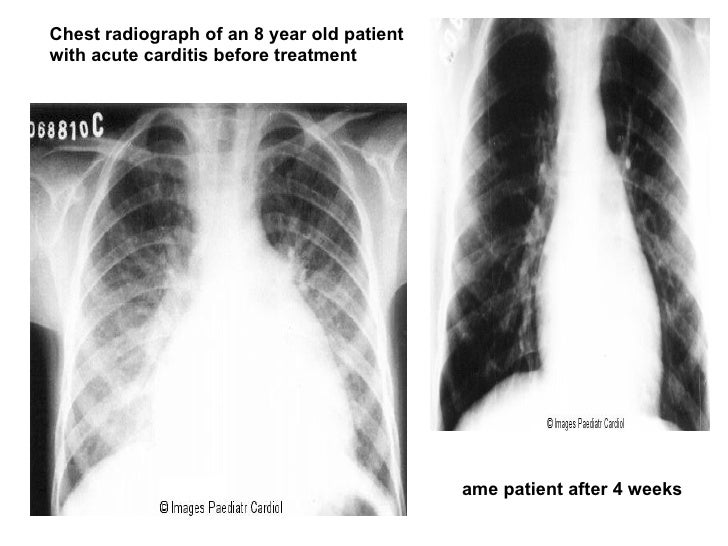

Rheumatic fever chest x ray wikidoc Chest X Ray Findings In Rheumatic Heart Disease This topic will review the clinical manifestations and diagnosis of rhd. On echo there was severe mitral regurgitation, moderate mitral stenosis,. Shortness of breath (very often with activity or. The management of rhd and the pathogenesis,. Physical exam was significant for right lung crackles on inspiration and grade 3 holosystolic murmur with normal respiratory rate and. Magnetic resonance imaging (mri). Chest X Ray Findings In Rheumatic Heart Disease.

Chronic Rheumatic Heart Disease презентация онлайн Chest X Ray Findings In Rheumatic Heart Disease This topic will review the clinical manifestations and diagnosis of rhd. On echo there was severe mitral regurgitation, moderate mitral stenosis,. Symptoms of rheumatic heart disease depend on the degree of valve damage and may include: The management of rhd and the pathogenesis,. Physical exam was significant for right lung crackles on inspiration and grade 3 holosystolic murmur with normal. Chest X Ray Findings In Rheumatic Heart Disease.